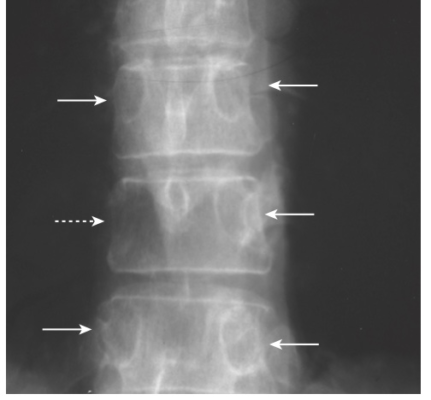

- Đa u tuỷ (Multiple myeloma), bệnh ác tính nguyên phát phổ biến nhất của xương ở người lớn, có thể xảy ra ở dạng đơn độc, thường thấy như một tổn thương lan rộng, như bong bóng xà phòng ở cột sống hoặc xương chậu (được gọi là u tương bào đơn độc) hoặc ở dạng lan tỏa với nhiều tổn thương tiêu xương, kiểu ấn lỗ (punched-out) trong các xương trục và đầu gần xương chi.

- Sau đó, ở dạng lan rải, có nhiều tổn thương huỷ xương có kích thước gần như nhau, nhỏ, khoanh tròn rõ ràng (được mô tả như ấn lỗ) hiện diện, thường không có phản ứng xơ cứng đi kèm quanh chúng (Hình 10).